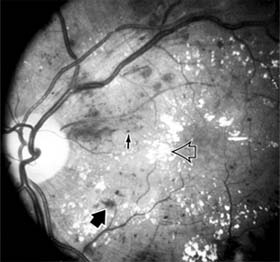

The visual and electrophysiologic dysfunctions associated with diabetes probably result from the local vascular abnormalities and the systemic metabolic effects of the disease to which the retina is subjected. A characteristic blue-yellow color vision abnormality develops, and hue discrimination may be impaired. Contrast sensitivity may be reduced in patients, even in the presence of normal visual acuity. Visual field testing may show relative scotomas corresponding to areas of retinal edema and nonperfusion, and abnormalities in dark adaptation have also been described. Electroretinographic abnormalities bear a relationship to the severity of retinopathy and may aid in predicting progression of retinopathy. Fluorescein angiography is invaluable in defining the microvascular abnormalities of diabetic retinopathy (Figures 10-21 and 10-22). Large filling defects of capillary beds-"capillary nonperfusion"-show the extent of retinal ischemia (Figure 10-23) and are usually most prominent in the midperiphery. The fluorescein leakage associated with retinal edema may assume the petaloid configuration of cystoid macular edema or may be diffuse. Other fluorescein abnormalities include vascular loops and intraretinal shunts. The focus of treatment in patients with nonproliferative diabetic retinopathy and no macular edema is treatment of hyperglycemia and intercurrent systemic disease. A controlled clinical trial has shown that aldose reductase inhibitor therapy does not prevent progression of diabetic retinopathy. Focal argon laser treatment of discrete points of retinal leakage in patients with clinically significant macular edema, principally defined as thickening of the retina at or within 500 0x0003bcm of the center of the macula, reduces the risk of visual loss and increases the likelihood of visual improvement (see Chapter 24). Eyes with diabetic macular edema that is not clinically significant should usually be monitored closely without laser treatment. Since macular edema may be present with little or no change in visual acuity and requires slitlamp biomicroscopic retinal examination for full evaluation, primary health care providers should recognize the importance of prompt and early referral of diabetic patients to the ophthalmologist.

Figure 10-21

Figure 10-21: Fluorescein angiogram in nonproliferative diabetic retinopathy shows microaneurysms (arrow) and perifoveal retinal vascular changes.

Figure 10-22

Figure 10-22: Late phase fluorescein angiogram shows hyperfluorescence typical of noncystoid diabetic macular edema.

Figure 10-23

Figure 10-23: Fluorescein angiogram shows hypofluorescence from capillary drop-out (arrows) typical of ischemic diabetic maculopathy.